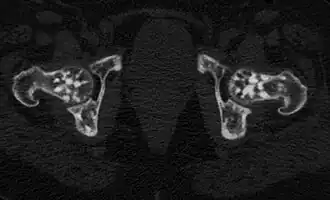

![]() Проявления остеопойкилии в костях таза и головках бедренных костей (компьютерная томограмма). | |

Заболевание является системным, проявляется очагами остеосклероза округлой и овальной формы, как правило приблизительно одинакового калибра, от 2 мм до 20 мм. Очаги могут располагаться практически во всех костях, однако наиболее часто выявляются в коротких костях запястья и предплюсны, метафизах и эпифизах длинных трубчатых костей (плечевых, бедренных) при интактности их диафизов[6].